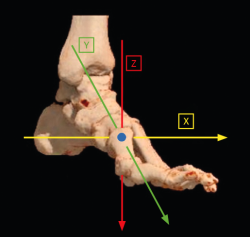

Históricamente, la etiología del hallux valgus con respecto a la estabilidad de la 1.ª ATMT ha sido objeto de mucho debate. La movilidad en el plano sagital fue sin duda lo que llamó la atención en las primeras investigaciones al respecto. Se han establecido asociaciones en el plano transverso entre la magnitud del AIMT y el ángulo del hallux valgus. La movilidad del plano coronal o frontal de la ATMT, presente en más del 80% de los hallux valgus, es necesaria para un aumento concomitante de ambos ángulos. Sin embargo, la inestabilidad aislada en el plano sagital de la ATMT no se ha podido demostrar como causa definitiva (Figura 3).

Figura 3. Representación de los ejes cartesianos de la primera articulación tarsometatarsiana y su capacidad de corregirse en los planos del espacio.